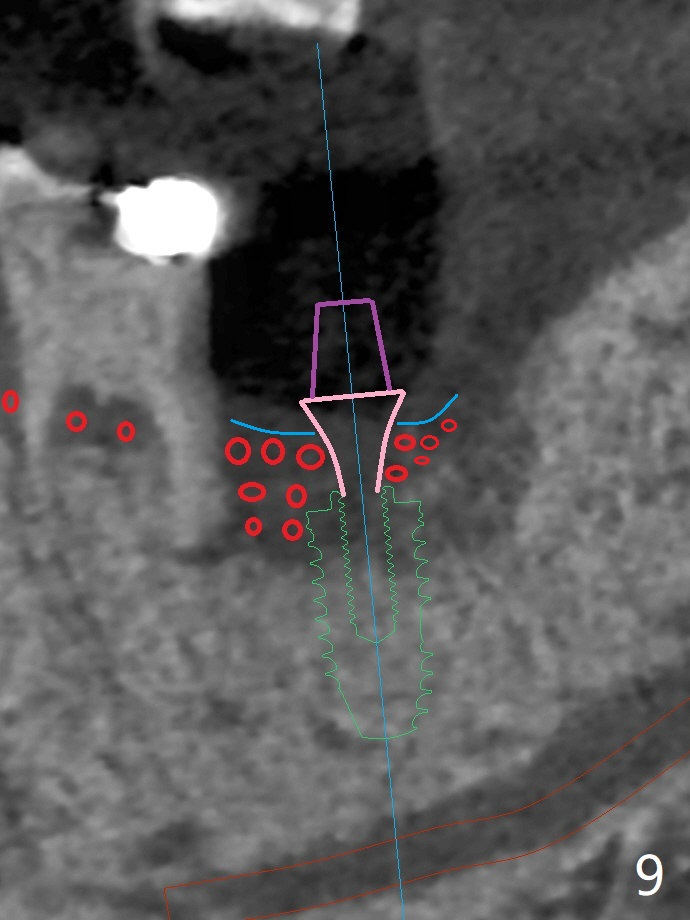

50岁男两年前不肯拔除左下7(图一),现在主动要求治疗(图二),需要做位点保留?怎么做的好?怎么收拾不动脑筋的惨剧(图三:仅远中牙槽窝植骨)?其实需要掀开近中粘骨膜(图四:箭头),然后植骨(红圆圈)。术后4.5个月近中缺损(图五:*),需要植牙植入很低(图六),离邻牙CEJ(<)很远。因此植体应该植入浅些(图七(CT矢状切面):箭头),离牙龈3毫米。放置袖3毫米(图八:粉红色)基台(紫色),然后在基台和植牙浅部植入粘性骨粉(图九:红圆圈)以及PRF膜(蓝线)。从冠状切面来看,颊侧(图十:B)需要多植骨,植牙前翻瓣(图十一:箭头),放置基台后(图十二),放置骨粉,膜,缝合。No Deviation 14 手术 Xin Wei, DDS, PhD, MS 1st edition 09/22/2020, last revision 03/02/2021